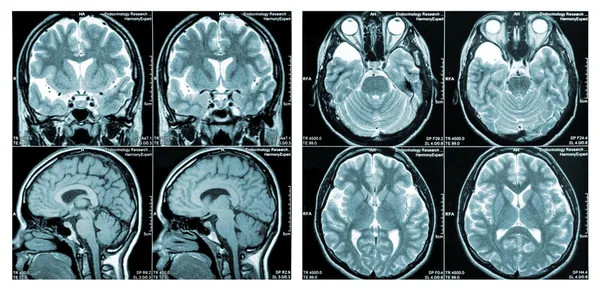

Beyin ve Sinir Cerrahisi Uzmanı Dr. Mansur Mamadov, genellikle beyinde aşırı su birikmesi olarak bilinen hidrosefali hakkında önemli bilgiler verdi. Beynin odacıklarında bulunan beyin-omurilik sıvısının miktarının artmasıyla kafa içindeki basıncın yükselip beynin zarar görmesine yol açtığını belirten Dr. Mamadov "Beyin omurilik sıvısı gün boyunca sürekli olarak yapılır ve geri emilir. Bu sıvı beyni ve omuriliği sarar ve devamlı bir dolaşım halindedir. Ayrıca üç temel görevi vardır: Beyin ve omuriliğe gelen darbelerin zararlı etkisini azaltmak, beynin beslenmesine ve atıkların taşınmasına yardımcı olmak, beyin ve omurilik arasında dolaşarak beyindeki basınç değişikliklerini düzenlemek" dedi.

Hidrosefaliye her yaşta rastlandığını ancak sıklıkla çocuklarda ve 60 yaşın üzerindeki kişilerde görüldüğünü söyleyen Dr. Mamadov yaklaşık 500 çocuktan birinde hidrosefali görüldüğünü, bu hastaların birçoğunda tanının doğumda, doğum öncesinde veya erken bebeklikte konulduğunu ifade etti. Nadir olmakla birlikte genetik (kalıtsal) bozukluklara veya gelişimsel bozukluklara bağlı geliştiğini; sık rastlanan nedenlerinin ise "beyin içi kanamaları, kafa travmaları, beyin tümörleri, erken doğuma bağlı kanamalar ve menenjit" olduğunu sözlerine ekledi.